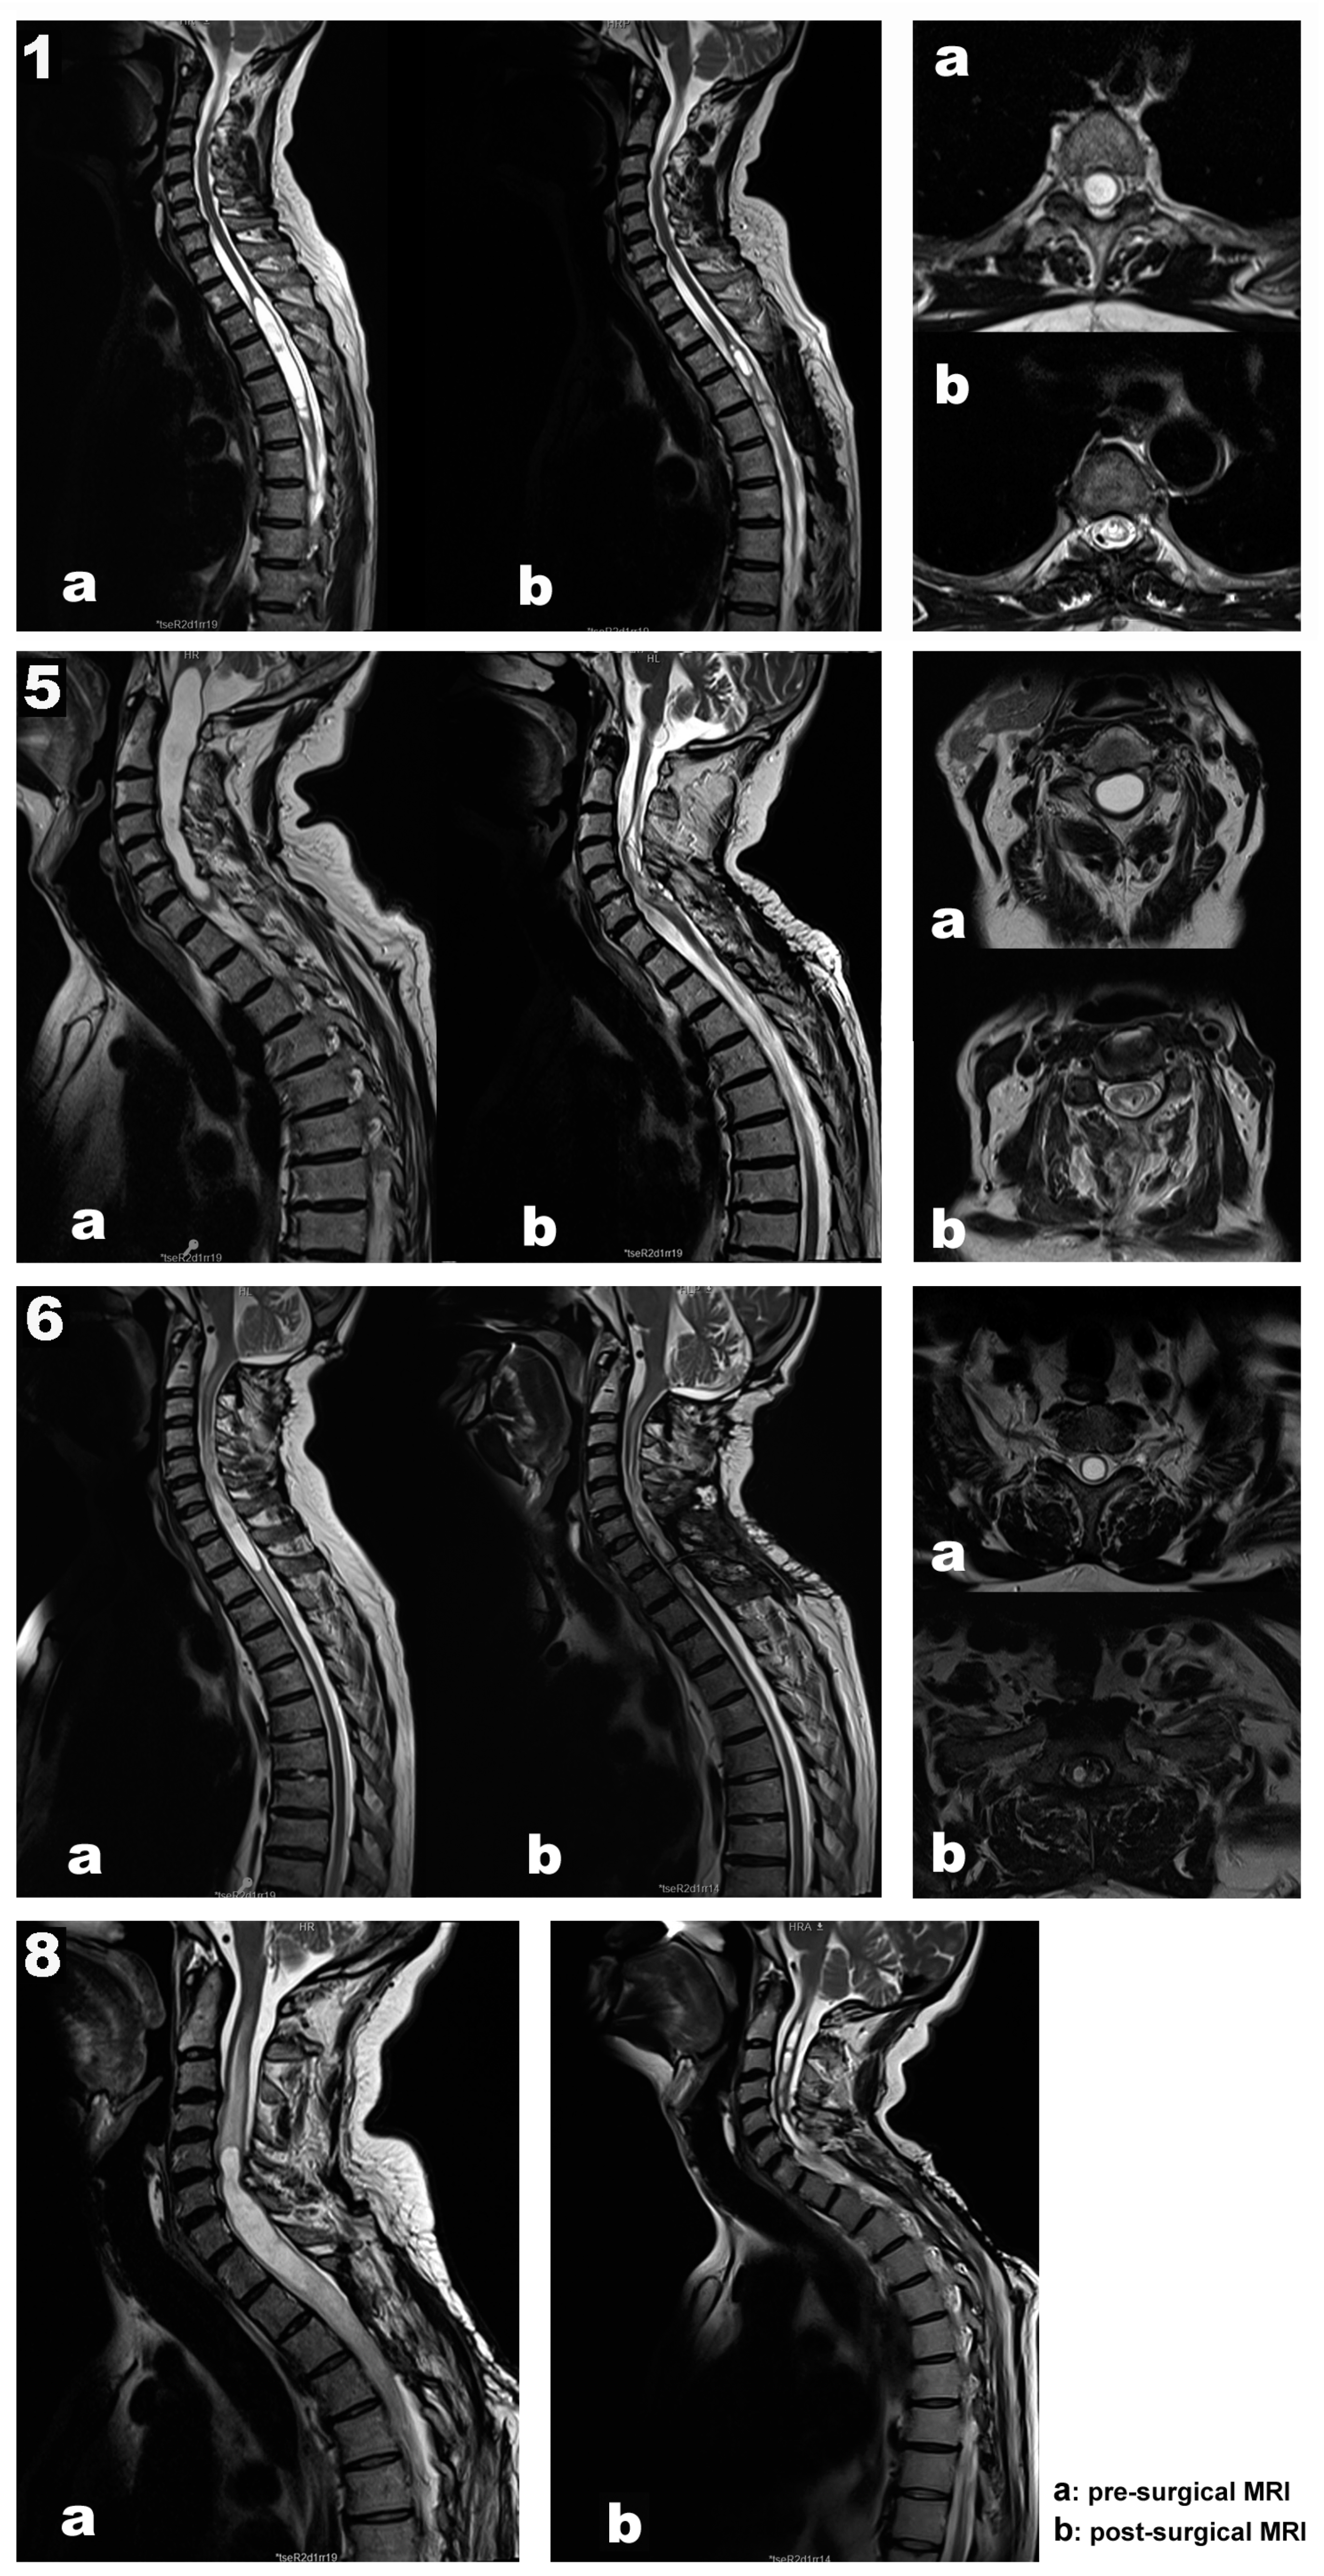

| 1 | 67 | Female | Post-traumatic | Th2–Th6 | Th4–Th5 laminectomy Left DREZ myelotomy Syringoperitoneal shunt | Loss of sensation of the left LL associated with left LL weakness | MEPs SEPs Free-EMG Root mapping | Transitory loss of left AHB MEP recovered after shunt repositioning SEPs remained stable throughout surgery Root identification | No new deficits Subjective clinical improvement |

| 5 | 70 | Male | Hemangioblastoma related | Medulla–C7 | C5–Th1 laminectomy Midline myelotomy Subarachnoid space reconstruction | Paresthesias in ULs Ataxia Mild muscle weakness in LLs | MEPs SEPs Free-EMG D-wave DCM | Transitory MEP decrement after prone position, recovered after neck reposition DCM for median raphe identification Transitory EMG discharges upon shunt placement Stable MEPs, SEPs, and D-wave | No new deficits Proximal UL and LL strength improvement, which persists one year later |

| 6 | 61 | Male | Chiari malformation | C6–Th2 | C7-Th1 laminectomy Left DREZ myelotomy Syringoperitoneal shunt | Progressive paraparesis Gait disturbances | MEPs SEPs Free-EMG DCM Root mapping | Prepositional baselines remains stable DCM for left DC and safe zone entry identification at DREZ Root identification SEPs and MEPs stable throughout surgery | No new deficits Distal left UL strength improvement One year later, progressive strength and sensory worsening |

| 8 | 48 | Male | Post-traumatic | Holocord | Reintervention (3 previous surgeries) C5–Th1 laminectomy Left DREZ myelotomy Syringoperitoneal shunt | Muscle weakness No more data is available | MEPs SEPs Free-EMG Root mapping | Prepositional baselines stable Root C7 and C8 mapping Sudden loss of left MEPs (ADM, APB, TA, and recto femoris) after shunt placement, not recovered by the end of the surgery | Worsening Hemiparesis (LLs > ULs) |